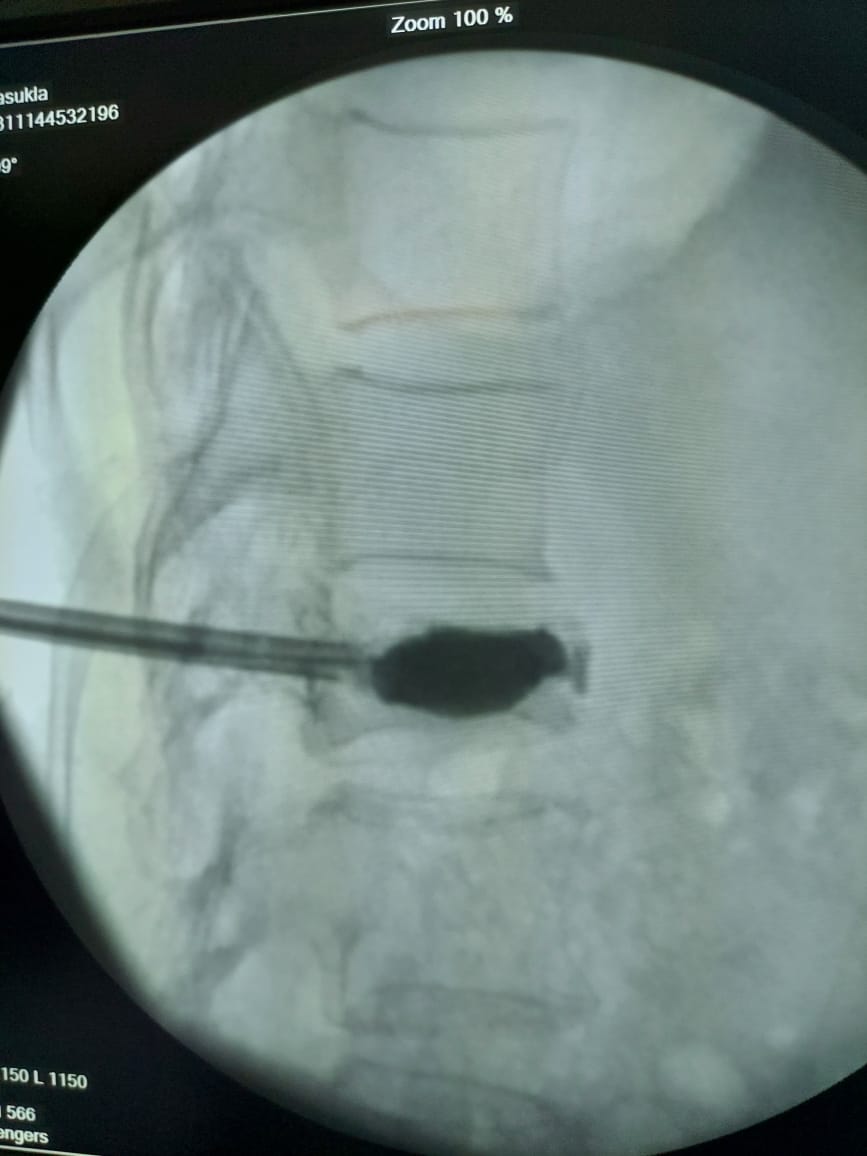

Vertebroplasty involves introduction of 1 or 2 needles into the fractured vertebral body from posterior side and then injection of a special cement into the fissures. This cement hardens after some time and hold the fractured segments together.

If there is significant reduction in the height of the vertebral body due to the fracture, we do a slight modification in this procedure which is then called as Kyphoplasty. Kyphoplasty involves first placement of a balloon in the fractured vertebral body through the needles and then injection of the cement into the balloon which not only stabilizes the fractured segment but also augments the vertebral body height.